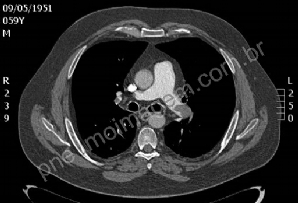

CASO CLÍNICO #41

Paciente tabagista com intensa dor no ombro direito e fraqueza muscular. Qual o diagnóstico? Deixe os seus comentários abaixo! ***** Smoking patient with intense right shoulder pain and muscle weakness. What is the diagnosis? Give your comments below!